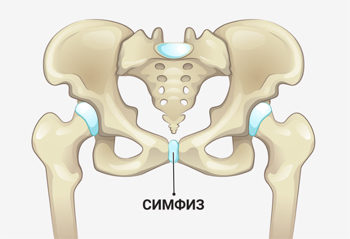

Симфиз — это соединение, состоящее из фиброзной или хрящевой ткани, которое связывает кости. Лобковый симфиз, в частности, представляет собой соединение верхних ветвей лонных костей, расположенное по средней линии тела.

Во время беременности правильным термином для описания данного патологического состояния является симфизиопатия. Этот диагноз ставится, если наблюдается чрезмерное размягчение хрящевой ткани, а расстояние между костями увеличивается более чем на полсантиметра.

У женщин, не находящихся в положении, расстояние между лонными костями составляет примерно 0,2 см. У молодых женщин в возрасте около 20 лет это расстояние может немного увеличиваться (до 0,6 см), после чего оно постепенно возвращается к нормальным показателям.